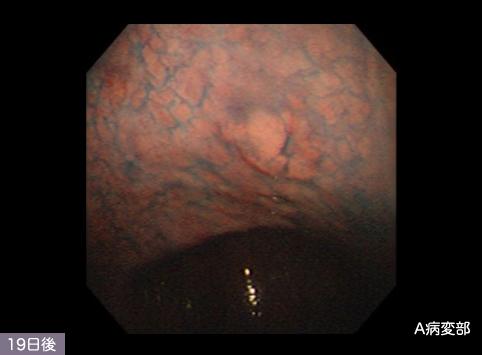

clasificación del pacienteTumor Epitelial Maligno/Cáncer a células en Sello de Anillo

parte(separada por órganos)estómago(región)/cuerpo

método de exámenEndoscopia

clasificación ectoscópica de tumoresTipo 0(tipo superficial)/Tipo IIa(IIa+IIb)

diámetro mayor del tumor35 - 40

grado de penetraciónm